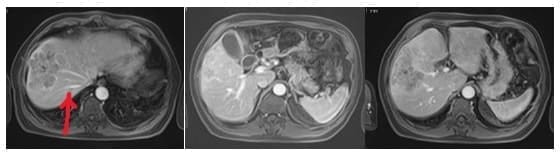

La ecografía mostró un hígado de contorno regular, sin evidencia de hepatopatía crónica, con una lesión compatible con hepatocarcinoma de 10,3 x 7 x 9,5 cm, comprometiendo los segmentos 4a, 5 y 8, sin lesiones metastásicas (figura 8), y la biopsia percutánea de hígado corroboró el diagnóstico de hepatocarcinoma.

Figura 8. Hepatocarcinoma de 10,3 x 7 x 9,5 cm comprometiendo los segmentos 4a, 5 y 8, con preservación de vena suprahepática derecha en su recorrido (flecha roja).

Se llevó en primera instancia a embolización supraselectiva portal de ramas de los segmentos comprometidos (figura 9).

Figura 9. Embolización supra selectiva de ramos portales hacia sectores centrales. En rojo ramo portal accesorio hacia sector anterior derecho, en azul ramo venoso del sector anterior derecho, en verde ramos portales izquierdos hacia segmento 4.